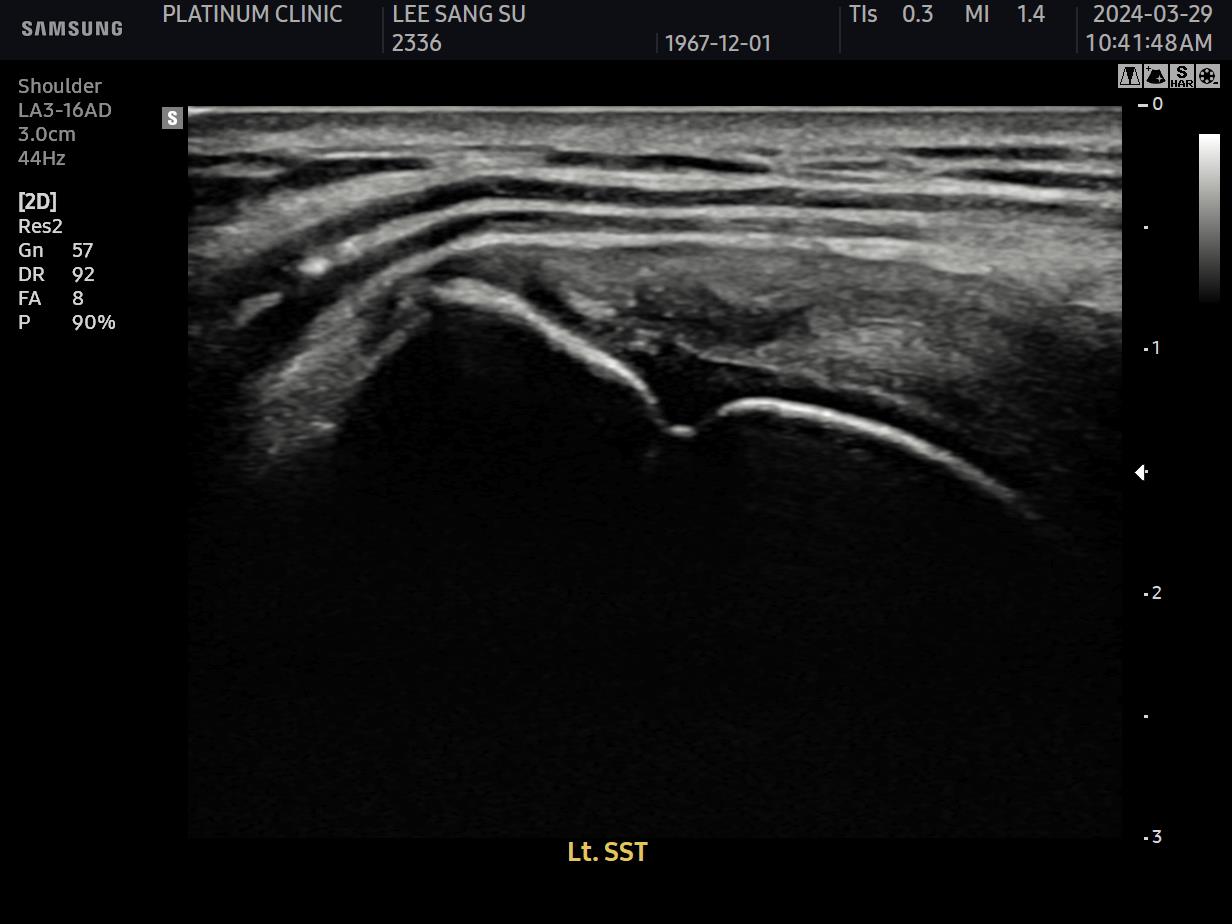

초음파 검사로 확인할 수 있습니다.

치료 전 초음파에서 검게 보이던 파열 부위가, 치료 후에는 정상 인대처럼 하얗게 보입니다. 이것이 구조적 회복의 증거입니다.

안 아파요"라는 주관적 느낌만으로 치료 완료를 판단하면 안 됩니다. 영상으로 확인된 구조적 회복이 있어야 진정한 치료입니다.

초음파 검사에서 손상 부위가 회복되었음이 확인되어야 합니다.

파열 부위가 재생되어 정상 에코(밝기)를 보임

인대 두께가 정상 범위로 회복됨

주변 염증 소견이 사라짐

초음파 결과:

이전에 검게 보이던 파열 부위가 하얗게 재생됨

주변 염증 소견 소실